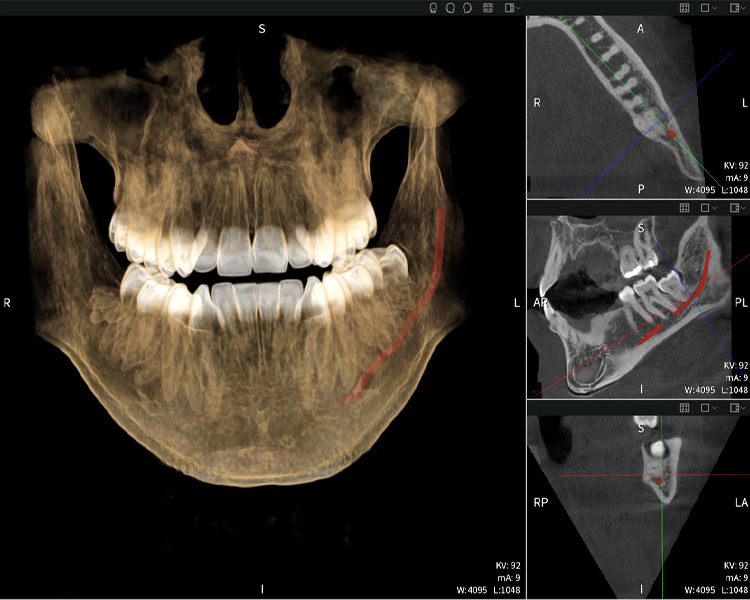

Figura b: Resultados de imagen de Seethrough Max, sobre un fondo negro.

Figura b

Las figuras b–d muestran varias vistas de una reconstrucción 3D de la mandíbula, proporcionando una visión general completa de la anatomía mandibular, la posición de los nervios en relación con los dientes y permitiendo evaluar la simetría y alineación dentaria.